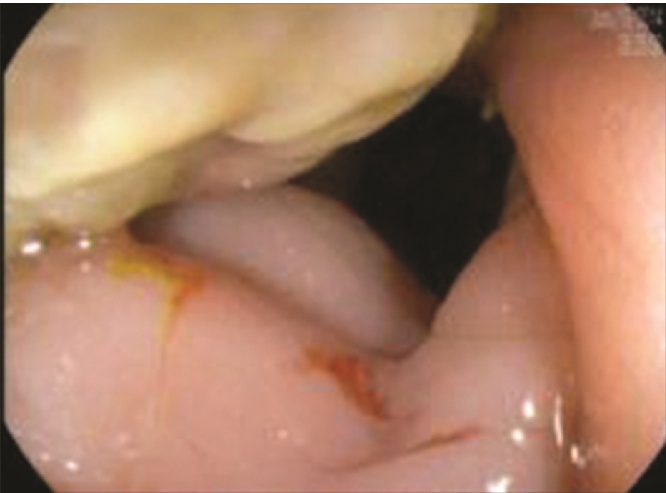

He subsequently presented to his primary care physician complaining of two weeks of nausea, vomiting, abdominal distention, hematochezia, and a decrease in stool caliber. Examination revealed a soft, non-tender, but distended abdomen, and a computed tomography scan showed an infiltrative mass in the distal sigmoid colon (Fig. 1). The patient was admitted and underwent colonoscopy, which revealed a near obstructing, circumferential, ulcerated mass in the lumen of the sigmoid colon, approximately 20 cm from the anal verge (Fig. 2, Fig. 3). The biopsy was non-specific and showed fragments of a fibrinopurulent exudate and normal colonic mucosa without evidence of malignancy.

Colonoscopy image showing the near obstructing, circumferential mass in the sigmoid colon.

Fig. 3.

Colonoscopy image showing the ulcerated mass in the sigmoid colon.